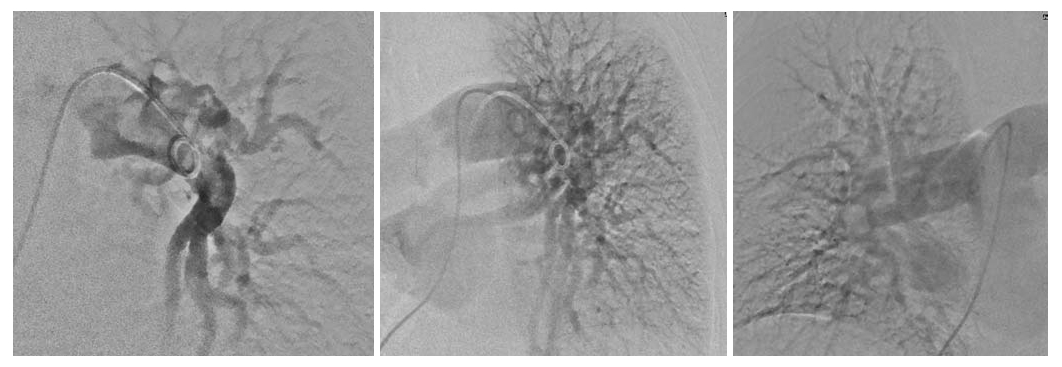

12.07.11 в связи с подозрением на ТЭЛА была выполнена ангиопульмонография (АПГ). Слева в нижних отделах ствола с переходом на нижнедолевую ветвь обнаружен массивный тромбоэмбол, необтурирующий, со свободной перфузией лишь верхнедолевой ветви. Справа в дистальных отделах ствола правой легочной артерии с переходом на среднедолевую и нижнедолевую ветвь определяется массивный тромбоэмбол с флотацией дистального проксимального конца. Перфузия верхней и нижней доли сохранена из-за необтурирующего положения тромбоэмбола. Заключение: двусторонняя массивная ТЭЛА. Индекс Миллера 24 балла. Легочная гипертензия 2 степени (рис.1).

Рис 1. Ангиопульмонография левого и правого легкого больной О. до проведения тромболизиса.

13.07.11 на контрольной ангиограмме по сравнению с исследованием от 12.07.11 после проведенного тромболизиса актилизе 100 мг отмечается выраженная положительная динамика. Справа - полный лизис тромбоэмболов, просвет долевых и сегментарных артерий свободен. Слева в бифуркации левой легочной артерии определяется круглый остаточный тромбоэмбол, прилежащий больше к устью нижнедолевой ветви, не нарушающий перфузии легкого, просвет долевых и сегментарных артерий свободен. Индекс Миллера снизился с 24 до 6 - 9 баллов (рис. 2).

Рис 2. Ангиопульмонография левого и правого легкого больной О. после проведения тромболизиса.